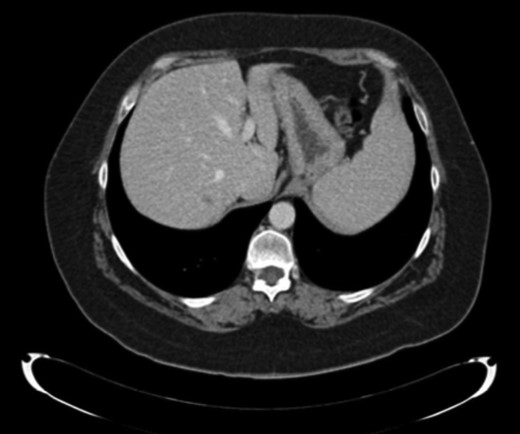

Ten months later, CT revealed two hepatic lesions (segment III of 3 cm and segment VII of 1 cm) (Fig. 2) The biopsy confirmed the original histology of SNUC. Chemotherapy with docetaxel 75 mg/m2, cisplatin 75 mg/m2 and 5 FU 750 mg/m2 every 3 weeks for 3 months was administrated. Because of minimal response was achieved after chemotherapy (Fig. 2) a non-anatomical metastasectomy was performed.

CT scan first relapse. Liver metastases: sIII and sVII 2.2 CT scan after neoadjuvant chemotherapy.